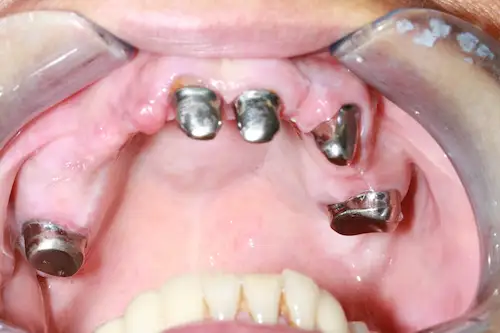

Der chirurgische Eingriff im Detail

Der Tag der Operation ist gekommen: Im ersten Schritt werden die noch vorhandenen Zähne gezogen sowie die Wurzeln und vereinzelte Zysten restlos entfernt. Dies erwies sich im vorliegenden Fall als extrem komplex und folgenreich: Beim Extrahieren gingen Teile der Knochenwände verloren, was einen deutlichen Mehraufwand beim Aufbau des Kieferkamms nach sich zog. Zuzüglich zu Knochenersatzmaterial verwendete Dr. Mintert dafür 2 Collagen Blöcke, 2 Membranen und 0,3 ml Emdogain. Letzteres dient der Entwicklung von zahnstützendem Gewebe. Auch Eigenknochen aus einem zweiten OP-Gebiet kam zum Einsatz. Im Oberkiefer wurde außerdem ein sogenannter Sinuslift durchgeführt, der – vereinfacht gesprochen – die Kieferhöhlen anheben soll. Nun waren die Grundlagen für den nächsten Schritt geschaffen: Eine eigens angefertigte Bohrschablone ermöglicht die navigierte Implantation. So fanden alle acht Implantate trotz ungeplanter Komplikationen ihren rechten Platz im Mundraum. Abschließend wird L-PRF Plasma, d.h. zentrifugiertes Eigenblut eingebracht, um die Wundheilung zu unterstützen. Als Zahnersatz werden zwei festsitzende Keramikbrücken gewählt und auf künstliche Keramikaufbauten geklebt. Diese wiederum sind mit jeweils vier Implantaten verschraubt.

Röntgenaufnahme - nach OP - All-on-Four

All-on-Four Zahnersatz nach OP - Patientenansicht